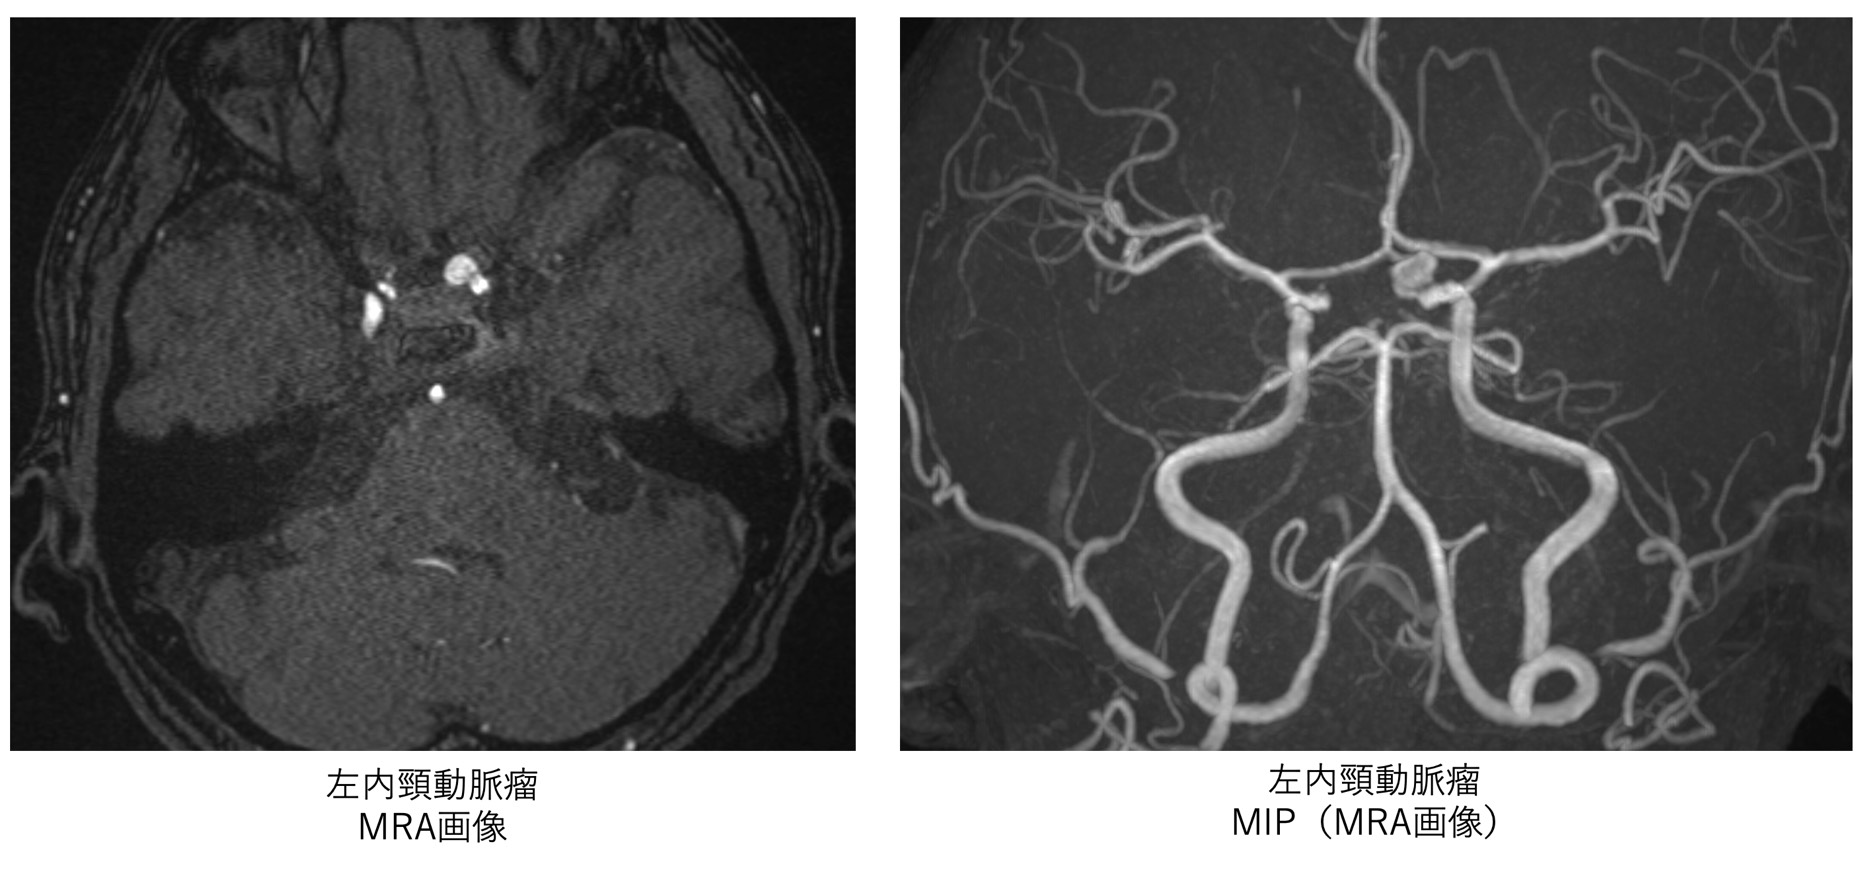

初学者のためのMRIの読み方 | 高橋睦正 |本 | 通販 | Amazon